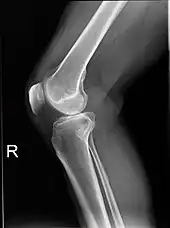

Plain radiograph of the right knee

Projectional radiography is the practice of producing two-dimensional images using X-ray radiation. Bones contain a high concentration of calcium, which, due to its relatively high atomic number, absorbs X-rays efficiently. This reduces the amount of X-rays reaching the detector in the shadow of the bones, making them clearly visible on the radiograph. The lungs and trapped gas also show up clearly because of lower absorption compared to tissue, while differences between tissue types are harder to see.

Projectional radiographs are useful in the detection of pathology of the skeletal system as well as for detecting some disease processes in soft tissue. Some notable examples are the very common chest X-ray, which can be used to identify lung diseases such as pneumonia, lung cancer, or pulmonary edema, and the abdominal X-ray, which can detect bowel (or intestinal) obstruction, free air (from visceral perforations), and free fluid (in ascites). X-rays may also be used to detect pathology such as gallstones (which are rarely radiopaque) or kidney stones which are often (but not always) visible. Traditional plain X-rays are less useful in the imaging of soft tissues such as the brain or muscle. One area where projectional radiographs are used extensively is in evaluating how an orthopedic implant, such as a knee, hip or shoulder replacement, is situated in the body with respect to the surrounding bone. This can be assessed in two dimensions from plain radiographs, or it can be assessed in three dimensions if a technique called '2D to 3D registration' is used. This technique purportedly negates projection errors associated with evaluating implant position from plain radiographs.[101]